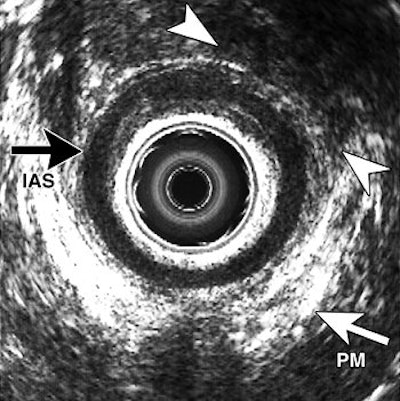

| A transverse endoanal US image (b) obtained in same patient shows EAS defect at upper edge (arrowheads) in proximal anal canal. This finding was confirmed during anal sphincter repair, which revealed an anterior EAS defect. Top of the figure is anterior. IAS = internal anal sphincter; PM = lower edge of puborectal muscle. Figure 3a,b. Dobben AC, Terra MP, Slors JFM, et al. "External anal sphincter defects in patients with fecal incontinence: comparison of endoanal MR imaging and endoanal US." Radiology 2007; 242: 463-471. |